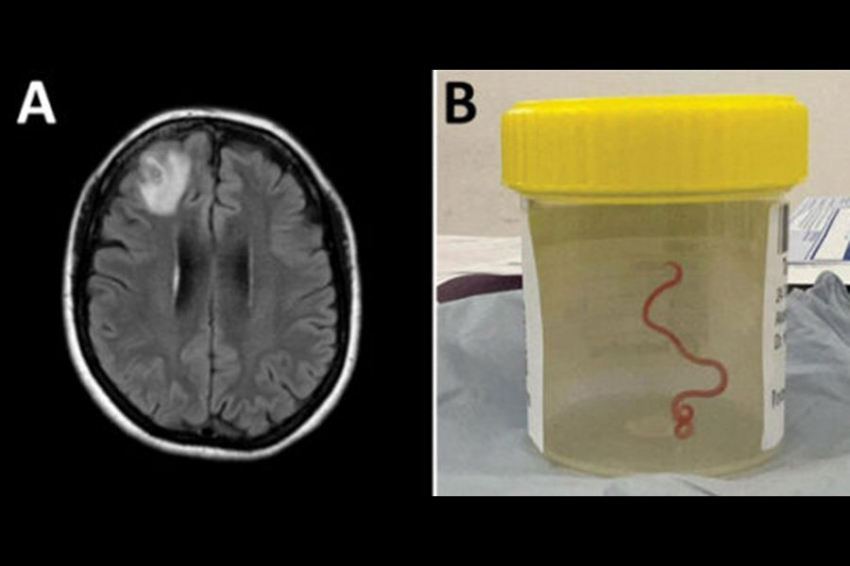

Фото из открытых источников Во время операции на открытом мозге 64-летней женщины врачи больницы Канберры заметили ...